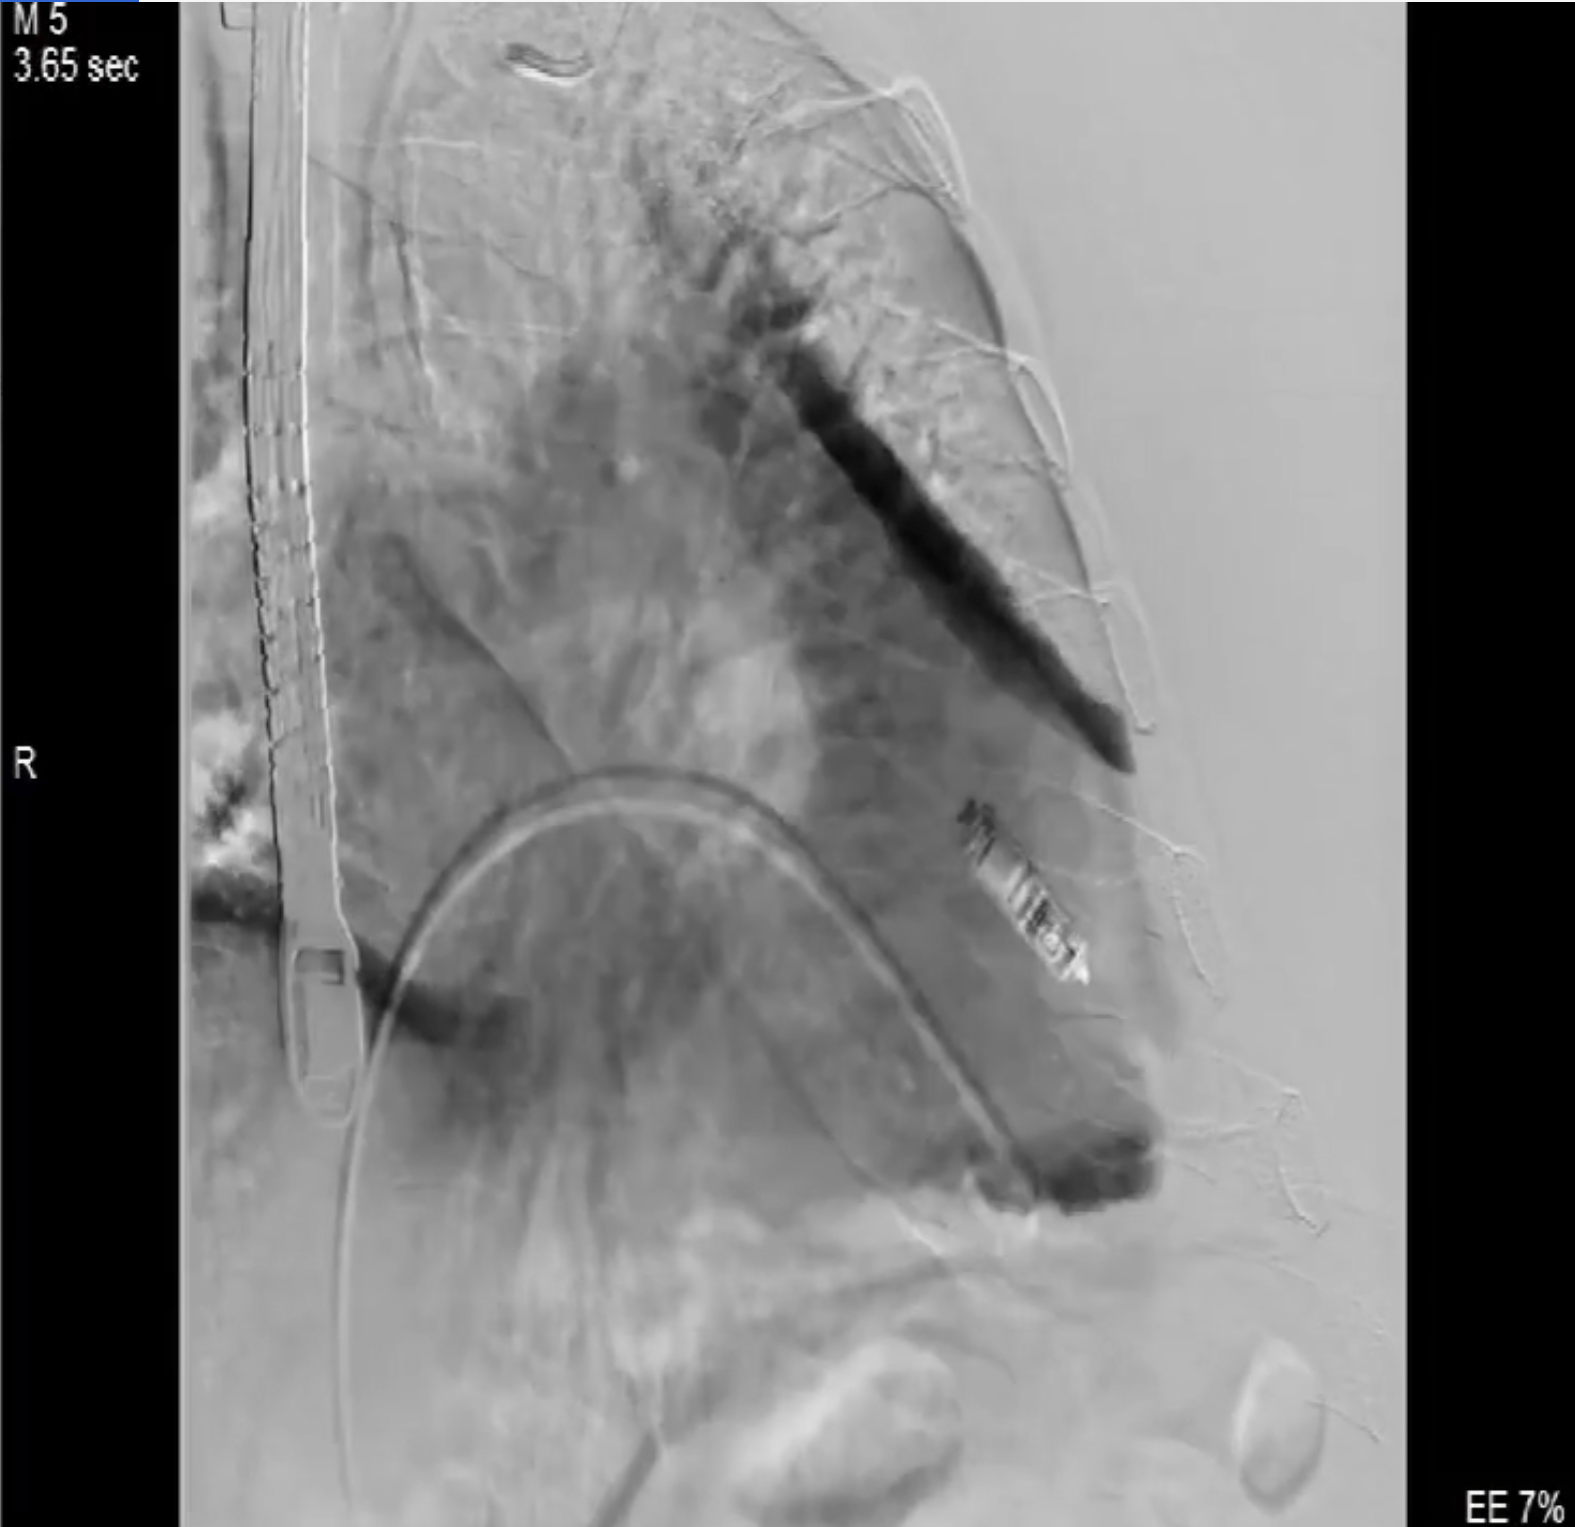

術中影像

術前DSA造影可見三尖瓣大量返流呈瀑布樣,右室偏間隔側可見無導線起搏器一枚。

術中經食道超聲輔助下可見LuX-Valve Plus夾持件抓捕瓣葉狀態(tài)良好,夾持件在位,室間隔錨定位置良好,假體瓣膜整體錨定狀態(tài)穩(wěn)固。

術后即刻經食道超聲可見,三尖瓣假體瓣膜位置合適,牛心包瓣葉運動狀態(tài)良好,開閉正常,瓣周及瓣葉對合緣處未見明顯返流,心電圖及心包狀態(tài)較術前無明顯變化。

本次直播手術中,手術團隊在超聲與DSA等多維影像手段的支持下,精準嫻熟的完成LuX-Valve Plus瓣膜的植入,器械操作時間僅為30分鐘,瓣膜植入后術中即刻三尖瓣返流消失,多普勒超聲下無明顯瓣周漏或中心性返流,肺動脈壓正常,平均跨瓣壓差僅為1mmHg,人工瓣膜運動正常,術后1小時內該患者即安返病房。